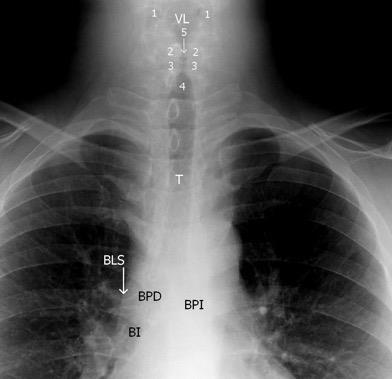

Línea del cuello

Fosa supraclavicular

Vías aéreas

Densidad pulmonar

Línea axilar

Sombras mamarias

Diafragmas

Partes blandas de la pared